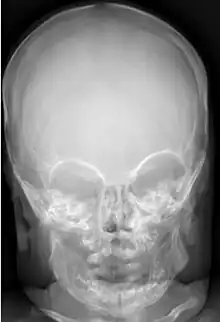

Infantile cortical hyperostosis (ICH) is a self-limited inflammatory disorder of infants that causes bone changes, soft tissue swelling and irritability. The disease may be present at birth or occur shortly thereafter. The cause is unknown. Both familial and sporadic forms occur. It is also known as Caffey disease or Caffey's disease.

An affected infant typically has the following triad of signs and symptoms: soft-tissue swelling, bone lesions, and irritability. The swelling occurs suddenly, is deep, firm, and may be tender. Lesions are often asymmetric and may affect several parts of the body. Affected bones have included the mandible, tibia, ulna, clavicle, scapula, ribs, humerus, femur, fibula, skull, ilium, and metatarsals. When the mandible (lower jaw bone) is affected, infants may refuse to eat, leading to failure to thrive.

Radiographs initially show layers of periosteal new bone formation with cortical thickening. Periosteal new bone may cover the diaphysis of the bone, causing an increase in diameter of the bone. Over time, the periosteal new bone density increases, becoming homogeneous with the underlying cortex. Eventually, the bone remodels and resumes a normal appearance.

Most infants with infantile cortical hyperostosis are diagnosed by physical examination. X-rays can confirm the presence of bone changes and soft tissue swelling. Biopsy of the affected areas can confirm the presence of typical histopathological changes. No specific blood tests exist, but tests such as erythrocyte sedimentation rate (ESR) and alkaline phosphatase levels are often elevated. A complete blood count may show anemia (low red blood cell count) and leukocytosis (high white blood cell count). Other tests may be done to help exclude other diagnoses. Ultrasound imaging can help diagnose prenatal cases.